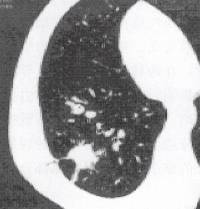

CT图像上胸膜凹陷常呈线形影,位于肺内病灶与胸膜之间,在常规层厚、间隔1Omm 图像上一般多表现为1条,以一小三角形止于胸膜面,亦可呈喇叭口状,尖端与线状影相 连,线状影另一端连于肺内病灶,部分病例见线状影与病灶棘状突起相连。线状影为凹入的 脏层胸膜相粘形成。斜裂胸膜凹陷在CT上仅表现为局部向病灶侧移位,无喇叭口状阴影形 成。典型的胸膜凹陷征是近脏层胸膜面见小三角形影或小喇叭状阴影,三角形的底部在胸 壁,尖指向结节,结节与三角形影之间可为线状影相连(图2、图3)。

由于扫描层面所处胸膜凹陷位置不同有时只显示线状影、有时线状影与贴近胸膜面小三 角形影同时见于相同层面,多数以肺窗观察为佳,少数也同时见于纵隔窗。有的胸膜凹陷出 现于自病灶引向胸膜的多数条影中,与三角形影相连的一条才是真正胸膜凹陷。相邻层面见 胸膜凹陷可有粘连,胸膜凹陷旁见肺气肿、肺不张。由于受部分体积效应的影响,致胸膜凹 陷在脏层胸膜面形成的三角形影显示不佳。从CT角度研究,胸膜凹陷线状影粗细、密度可 不一致,故胸膜凹陷在不同的技术上显示有所不同,条状影见于肺窗者,病理提示几乎无或 轻度胸膜增厚,多见于肺癌。而双窗均见者都有较明显胸膜增厚,特别是纵隔窗示线形影而 肺窗上呈一片模糊影,则高度提示炎性病变。

图2右下肺癌,肿瘤M与邻近 胸内壁间见两条线状影,与胸壁 相连处见喇叭状(箭示)

图3右下肺癌,HRCT四幅图像

(a)示扫描层处凹陷中心边缘,两条线影相距较远; 医学百科网 | YxBaike.Com

(b)示扫描层近凹陷中心,两条线影距离靠近;

(c)、(d)示扫描层渐近凹陷中心